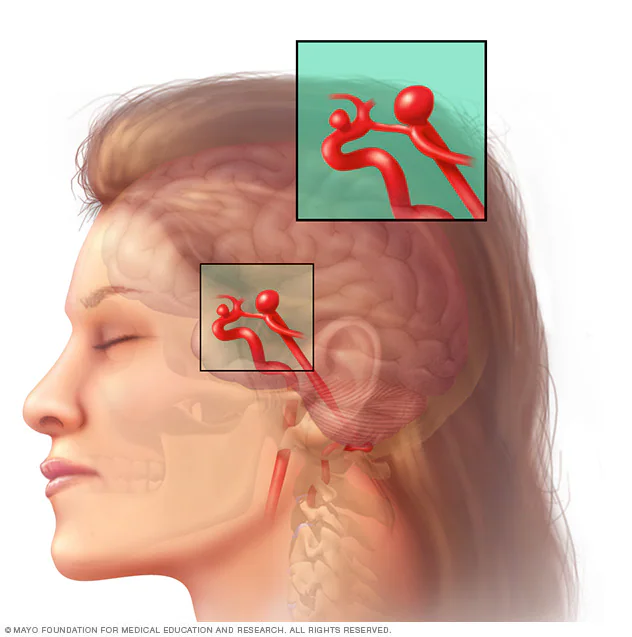

O que é aneurisma cerebral?

Um aneurisma cerebral é uma pequena “bolha” que se forma na parede de um vaso do cérebro. Essa parte da parede fica mais fina e mais frágil, como um ponto de fraqueza no encanamento.

Na maioria dos casos, o aneurisma é pequeno, silencioso e não causa sintomas.

Ele pode existir por muitos anos sem que a pessoa saiba. Geralmente, o aneurisma é descoberto por acaso, em exames feitos por outros motivos, como uma investigação de dor de cabeça, tontura ou esquecimento.

A maior preocupação é o risco de rompimento, ou seja, de “estourar”. Quando isso acontece, pode causar um sangramento grave no cérebro e exige atendimento médico imediato.

Mas é importante reforçar: a maioria dos aneurismas não rompe.

Muitos são apenas acompanhados, sem necessidade de cirurgia, dependendo do tamanho e da localização.

Entender o que é um aneurisma ajuda a diminuir a ansiedade. Quando sabemos como ele funciona e quais são os riscos reais, é mais fácil lidar com a situação com clareza e segurança.

Aneurisma não roto

É quando existe uma parte mais fraca na parede do vaso do cérebro, que forma uma bolha, como se fosse uma bexiga ou um ponto frágil no cano.

Dizemos aneurisma não roto quando essa “bexiga” não estourou.

Na maioria das vezes, a pessoa não sente nada e descobre o aneurisma por acaso, em exames feitos por outros motivos.

Muitos aneurismas nunca rompem e podem apenas ser acompanhados, com consultas e exames periódicos com o neurologista.